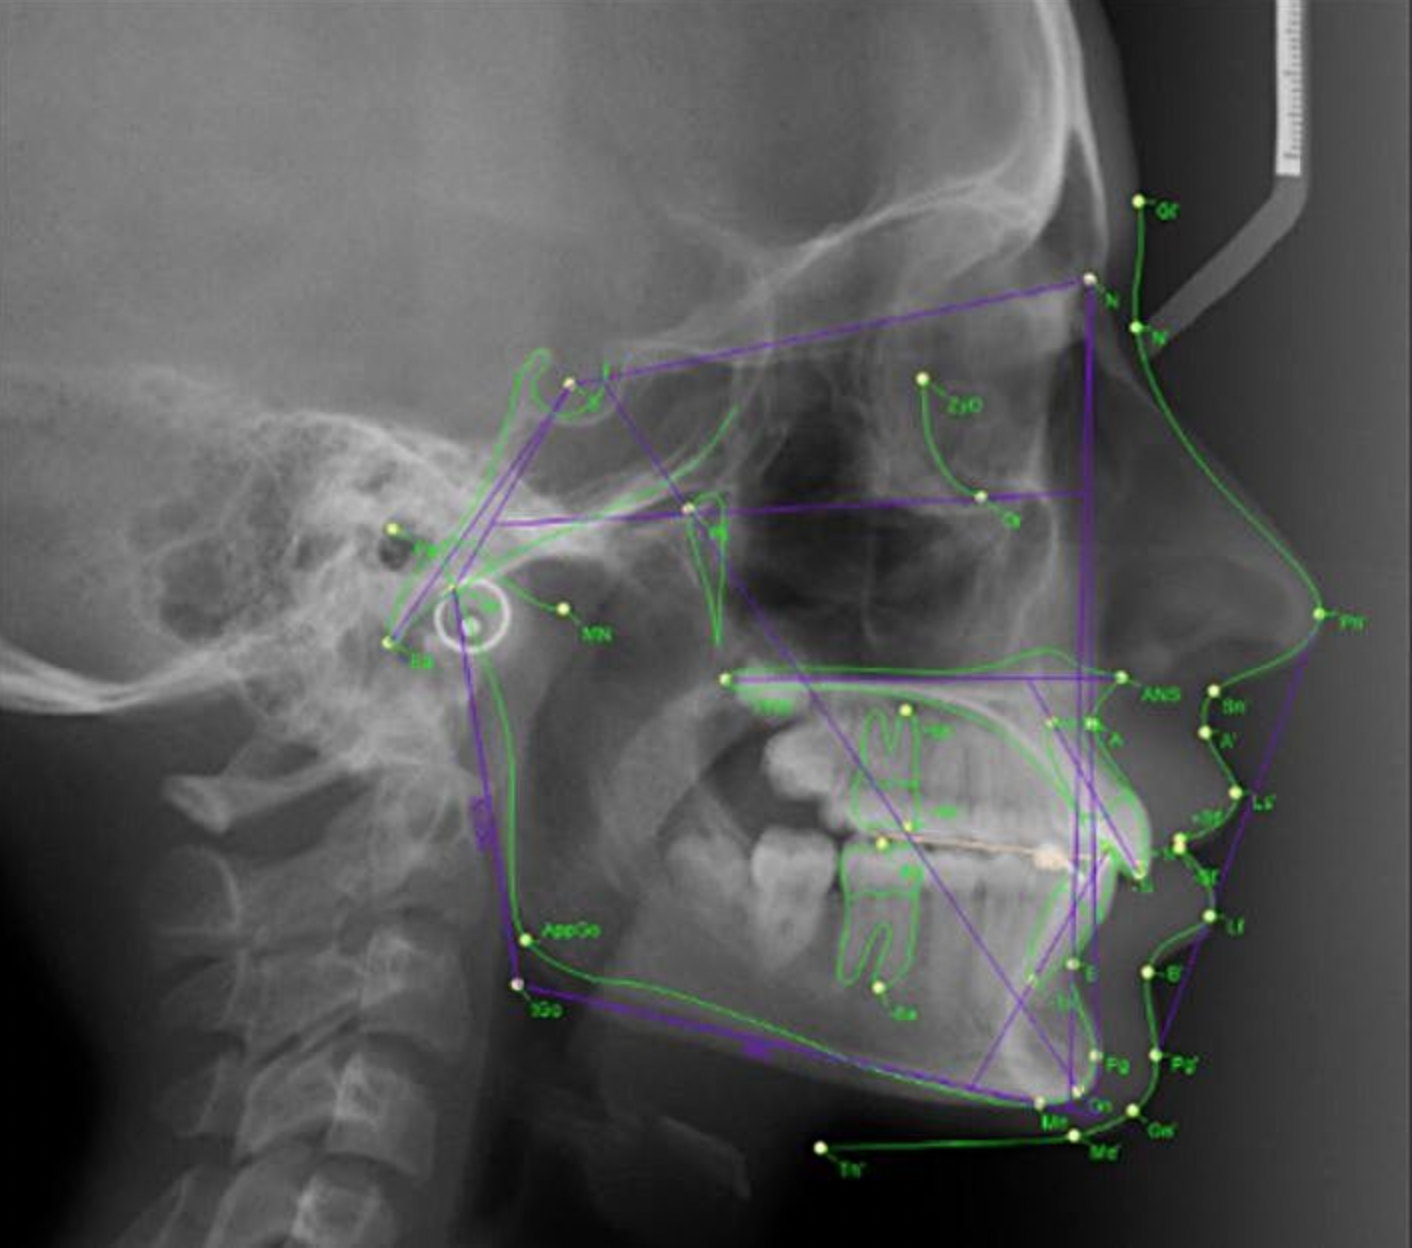

Пример цефалометрического анализа в 2D-формате

В более классическом двухмерном формате расчеты проводятся на обычных снимках ТРГ (телеренгенограммы) в прямой и боковой проекциях. Однако данный метод дает неполную информацию и имеет ряд недостатков и ограничений. Могут возникать проекционные наложения костно-анатомических структур, повышается вероятность в погрешностях расчетов.